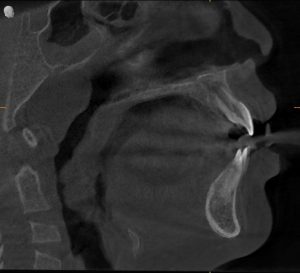

Clinical Evaluation: What We Observed

Facial & Postural Signs

- Forward head posture

- Tired-looking eyes with dark under-eye circles

- Narrow facial structure

Dental & Jaw Findings

- Narrow upper jaw

- Crowding of upper front teeth

- Deep, high-arched palate

- Early crossbite

- Tongue resting low in the mouth

Airway & Breathing Findings

- Snoring 4–5 nights per week

- Persistent mouth breathing

- Enlarged tonsils (Grade II–III)

- Nasal congestion

- Restless, poor-quality sleep

These findings strongly pointed toward Pediatric Sleep-Disordered Breathing.

Diagnosis

Tatvik was diagnosed with:

- Airway-related maxillary constriction

- Pediatric sleep-disordered breathing

- Chronic mouth breathing habit

- Low tongue posture

- Early orthodontic malocclusion